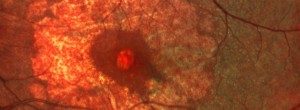

MANTRA: evaluación de la asociación entre la sensibilidad y el flujo retiniano en la DMAE